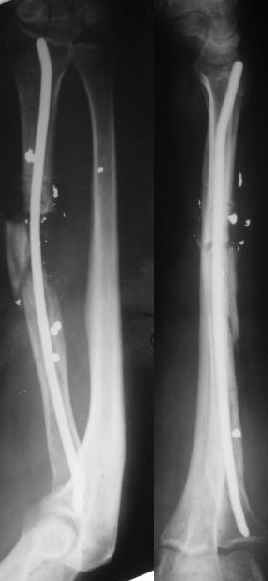

Мужчина 36 лет 5 мес. назад получил дробовое ранение правого предплечья с переломом лучевой кости, повреждением лучевой артерии и срединного нерва.

В больнице по месту жительства обрабатывали рану,сделали несвободную кожную пластику, синтезировали спицей интрамедуллярно, потом убрали. Свищей нет. Линейный рубец по лучевой стороне, приживший лоскут по ладонной (см. картинку).Cращение не произошло (см. снимок).Нейрохирурги что-то надеются сделать, но условием ставят стабилизацию лучевой кости.Какой вариант тут предпочесть? Представляется оптимальным аппаратом дозированно подправить длину и ось, и закрыто ввести интрамедуллярный стержень. Не особо даже рассчитывая на сращение, а только восстановить форму и длину кости, и создать "эндопротез диафиза". Или подумать про какие-то другие варианты?A male 36 years old 5 month ago sustained a gun-shot wound with the radial fracture and lesion of a.radialis and n.medianus. Debridement was performed at the initial hospital, full-thickness skin grafting and intramedullary fixation of the radius by a small wire, which later was removed. No sinuses and signs of infection to date. A linear scar on the radial side and the healed flap (see image). Healing was not reached (see x-rays).Neurosurgeons hope to do something with the peripheral nerves but only in case of stabilization of the radius.Which treatment modality should be preferred? I would perform gradual alignment with the Ilizarov, and perform secondary closed nailing. Even not to expect to reach union, just to restore length andalignment with the "shaft endoprosthesis". Or it is worth to think about other options?